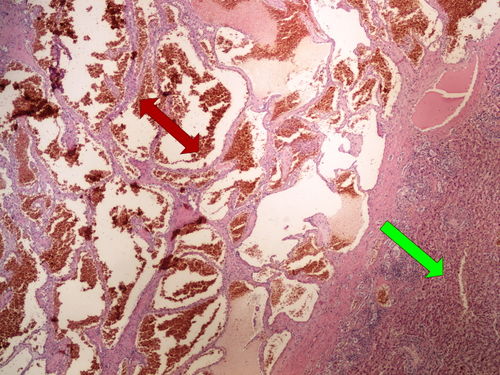

Slide no.1 and no.2 - kavernósní hemangiom jater

Structures to know

- hemangiom

- jaterní parenchym

- blandní epitelie - stěna hemangiomu